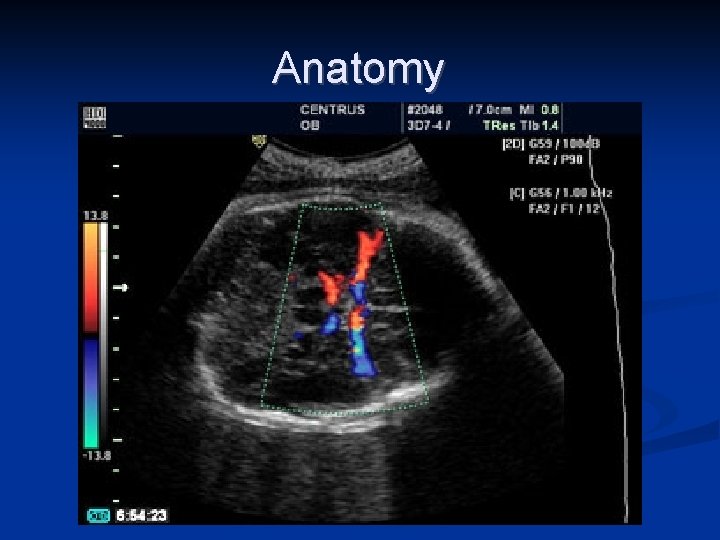

Anatomy